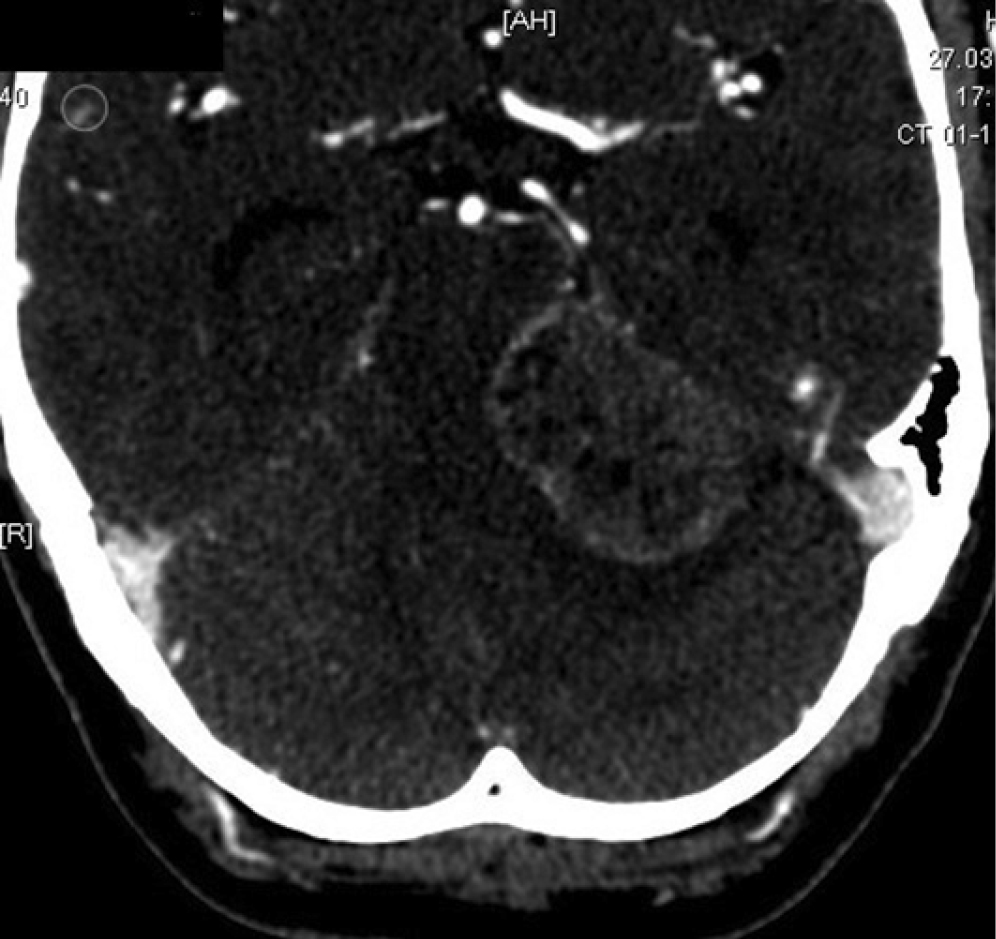

M. Samii et al. emphasize that peritumoral edema in patients with VS indicates tumor hypervascularity and a tendency to form tumor bed hemorrhage in the postoperative period [32]. According to preoperative MRI findings, our patient had no peritumoral edema. However, MSCT data (Fig. 4) indicated hypodense changes in the region of the pons and in the adjacent regions of the cerebellum.

Fig. 4. Preoperative axial contrast-enhanced head MSCT scan with a peritumoral hypodensity area.